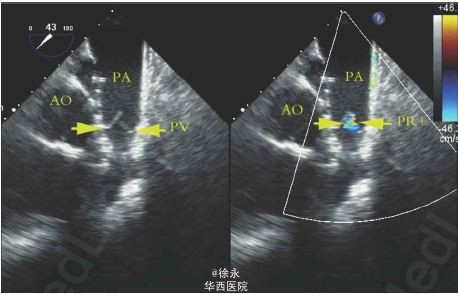

患者,女性,39 岁,25 年前因“法洛四联症”行外科治疗,近月出现活动后胸闷、心慌。超声心动图示外科术后补片下缘室水平残余分流,肺动脉瓣返流(重度)。住院期间先后行室缺残余漏封堵术+经皮导管肺动脉瓣置入术。